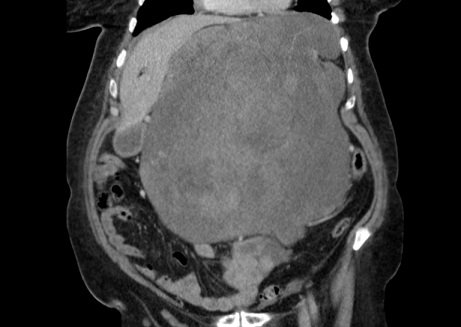

Bilgisayarlı tomografi görüntüleri tümörün ne denli büyük olduğunu gözler önüne serdi. Tümör karın içindeki organları mide, karaciğer ve bağırsakları kenara itmiş, diyaframdaki bir boşluktan göğüs boşluğuna sarkmıştı.